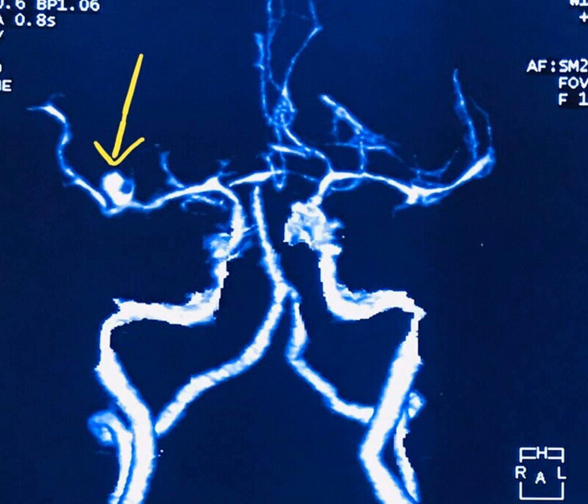

- Clip ligation of brain aneurysms (open microsurgery)